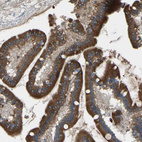

Immunohistochemical staining of human bone marrow shows moderate membranous positivity in hematopoietic cells.